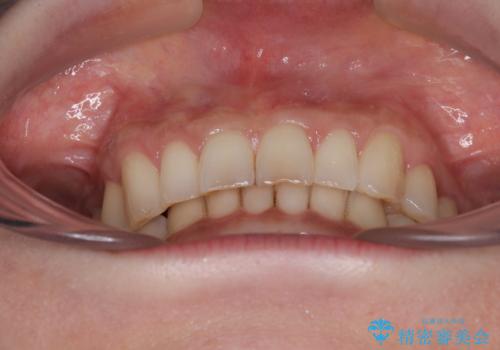

デコボコの歯とむし歯 インビザライン矯正治療とむし歯治療

- 奥歯が咬めないくらいに痛いとのことで来院された患者様です。

痛みの強い歯は、歯髄組織が強い炎症を起こしており、神経を取り除く必要であったため、速やかに根管治療を行いました。

その後、オールセラミッククラウンにて補綴治療を行う予定でしたが、処置した歯以外にも治療が必要と思われる歯があったり、デコボコした歯列も気になるとのことで、患者様希望によりインビザラインにてマウスピース矯正を行うこととしました。

まずは矯正治療前に必要なむし歯処置を行い、その後矯正治療を行ってから、最後にオールセラミッククラウンなどで補綴治療を行うこととしました。

咬合力が非常に強く、全体的に歯が擦り減っている状態であったので、理想的な咬み合わせを達成することは難しく、また咬合力が強い方のマウスピース矯正は、思い通りに動かないことがあるため、ワイヤー矯正の方が望ましいように思えました。

治療途中で2年強、体調を崩されて通院ができなくなってしまったため、必ず通院が必要なワイヤー矯正ではなく、マウスピース矯正で結果的には無事に治療を終えることができました。